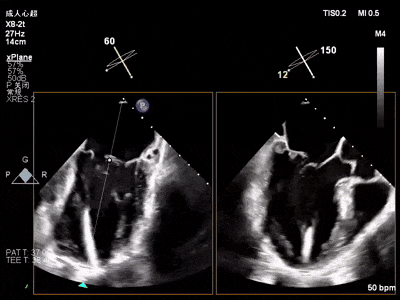

术前术后对比图

术前

术后

术后,出院检查报告显示:夹子位置固定,二尖瓣轻度反流,左室稍大,LVEF值正常范围,左室壁运动分析未见明显异常(左室壁运动记分指数1分)